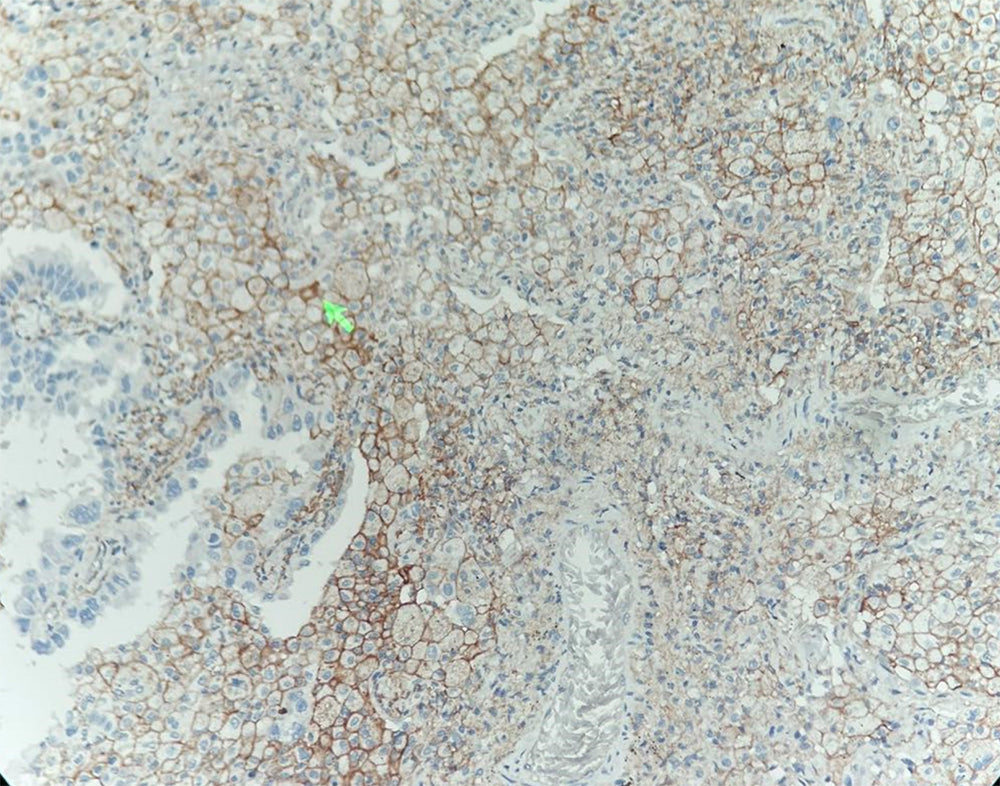

Localisation : Membrane cellulaire

PD-L1 est faiblement exprimé dans des conditions physiologiques normales sur les cellules présentatrices d’antigènes, certaines cellules épithéliales et des tissus immunologiquement privilégiés tels que le placenta et l’œil.

Il maintient la tolérance immunitaire périphérique en conditions normales et favorise l’échappement immunitaire tumoral en situation pathologique.

L’anticorps PD-L1 possède une double valeur dans l’évaluation du microenvironnement tumoral :

① une surexpression dans des tumeurs telles que le carcinome rénal et le carcinome ovarien indique des mécanismes d’évasion immunitaire et un pronostic défavorable ;

② sa détection permet de prédire l’efficacité des inhibiteurs PD-1/PD-L1 et de guider les décisions en immunothérapie.